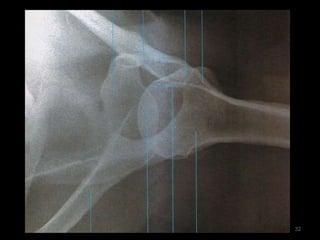

Ombro14

Incidência AP Ombro Rotação Neutra (1)15

32